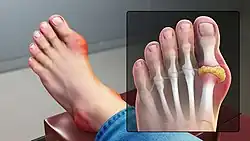

| Medical illustration of the big toe joint affected by gout | |

Gout (/ɡaʊt/ GOWT[7]) is a form of inflammatory arthritis characterized by recurrent attacks of pain in a red, tender, hot, and swollen joint,[2][8] caused by the deposition of needle-shaped crystals of the monosodium salt of uric acid.[9] Pain typically comes on rapidly, reaching maximal intensity in less than 12 hours.[5] The joint at the base of the big toe is affected (Podagra) in about half of cases.[10][11] It may also result in tophi, kidney stones, or kidney damage.[1]

Gout can present in several ways, although the most common is a recurrent attack of acute inflammatory arthritis (a red, tender, hot, swollen joint).[4] The metatarsophalangeal joint at the base of the big toe is affected most often, accounting for half of cases.[10] It can also involve midfoot structures, including the cuneiform bones.[16] Other joints, such as the heels, knees, wrists, and fingers, may also be affected.[4] Joint pain usually begins during the night and peaks within 24 hours of onset.[4] This is mainly due to lower body temperature.[1] Other symptoms may rarely occur along with the joint pain, including fatigue and high fever.[10][17]